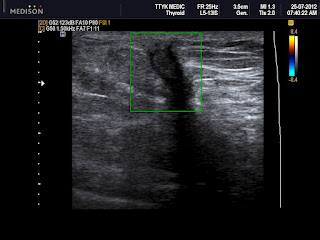

Scar tissue pain: What it feels like, why it happens, and treatment barque.qualitypoolsboulder.comRadioactive Seed Guided Lumpectomy | Radial Sclerosing Lesion | Radial

Radioactive Seed Guided Lumpectomy | Radial Sclerosing Lesion | Radial www.youtube.comHOW TO REDUCE MASTECTOMY SCAR PAIN & TENSION: My 4 Treatment Techniques